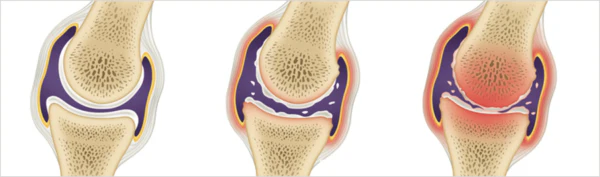

통풍은 주로 체내에 과다 축적된 요산으로 인해 발생합니다. 요산은 우리가 섭취하는 다양한 음식이 소화되어 최종적으로 대사된 후 혈액에 녹아 있다가 소변으로 배출되는 물질입니다. 일반적으로 혈액 내에서 요산은 정상 수준을 유지하며 배설됩니다. 그러나 통풍 환자는 혈액 내 요산이 과다하게 증가합니다. 이러한 과다 축적된 요산은 결정체로 변화하고, 이러한 결정체가 관절 내에 침착하여 염증을 일으킵니다.

통풍을 적절히 치료하지 않을 경우, 발작성 관절염의 빈도가 증가하고 침범하는 관절 수도 더 많아지며, 회복에 필요한 시간도 증가합니다. 반복적인 관절염은 관절을 점차 손상시키며, 만성적인 관절염으로 진행될 수 있습니다. 또한 통풍성 결절이라 불리는 덩어리가 관절 주위나 피부 조직에 나타날 수 있습니다. 이러한 결절은 요산 결정체의 덩어리로 어느 부분에서든 형성될 수 있으며, 주로 팔꿈치, 귀, 손가락, 발가락, 발목 등에서 발생할 수 있습니다. 때로는 요로 결석을 형성하기도 합니다.

1) 한 군데 관절(엄지발가락, 발목, 무릎 등)이 갑자기 붓고 빨갛게 변하며, 손을 움켜쥘 수 없을 정도로 심한 통증이 발생합니다.